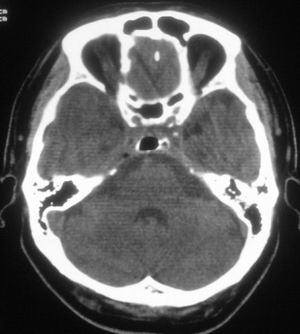

标题: CT20507:请问老师,鞍背正常吗??

空蝶鞍,正常变异

鞍背正常——为蝶窦过度气化所致。

是的,正常鞍区表现。鞍背骨质的低密度气体为蝶窦过度气化所致!

正常鞍区表现。鞍背骨质的低密度气体为蝶窦过度气化所致!

正常,鞍背骨质的低密度气体为蝶窦过度气化所致。